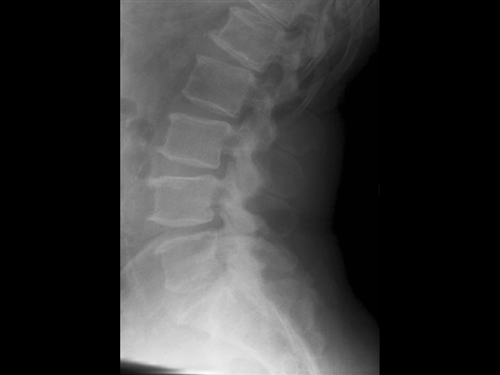

1. A 79-year old man falls sustaining a hyperextension injury to his neck. A lateral radiograph, CT scan and MRI are seen in Figures A through C. On motor examination, he has 3/5 strength in his deltoids, elbow and wrist flexors and extensors. He has 4/5 strength in his hip flexors, knee flexors, extensors, ankle dorsiflexors and plantarflexors. Sensation is preserved in both his upper and lower extremities as well as his sacral segments. Injury to which of the following tracts contributes greatest to his motor function deficits?

FIGURES: A

B

C

DISCUSSION: The clinical scenario describes a patient with central cord syndrome, resulting in an injury to his lateral corticospinal tract. Figures A through C show a spondylytic spine with central narrowing and CSF effacement that is worse at the C4-5 level. The lateral corticospinal tract is the main descending motor tract (Illustration A). Its anatomic position places the upper extermity motor tracts at greater risk than the lower extremity tracts. As such, injury to the lateral corticospinal tract is characterized by upper greater than lower extremity involvement and motor deficits being more pronounced than sensory deficits.